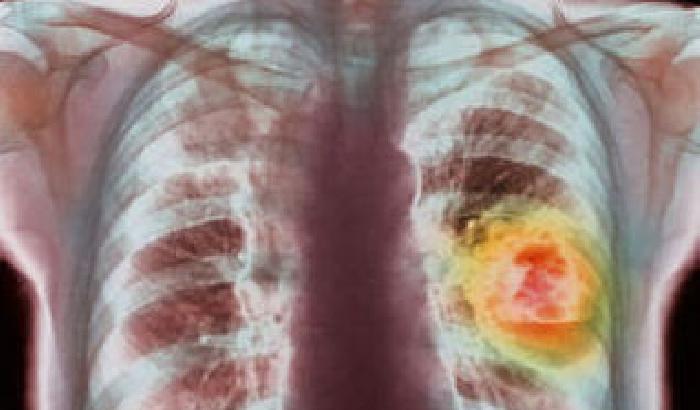

I vizi alla fine si pagano sempre. Soprattutto a Delray Beach, in Florida, dove i fumatori non sono ben accetti, e chi vuole lavorare come dipendente comunale deve dire addio per sempre alle sigarette. Oltre all’obiettivo di promuovere uno stile di vita più sano, il divieto di assumere persone con il vizio del fumo fa parte d’una nuova politica adottata dall’amministrazione per

risparmiare denaro.

I fumatori incalliti infatti possono costare sino a 12.000 dollari l’anno in più sul fronte dell’assistenza sanitaria. Si salveranno solo coloro che risultano essere stati assunti dalla città del Sunshine State prima del primo ottobre, ma anch’essi verranno comunque incoraggiati a smettere. A questo scopo sono stati creati corsi appositi, che si svolgono durante l’arco di tutto l’anno. Il Comune offre inoltre la prescrizione gratuita di cerotti e altri farmaci che aiutano a perdere il vizio del fumo.